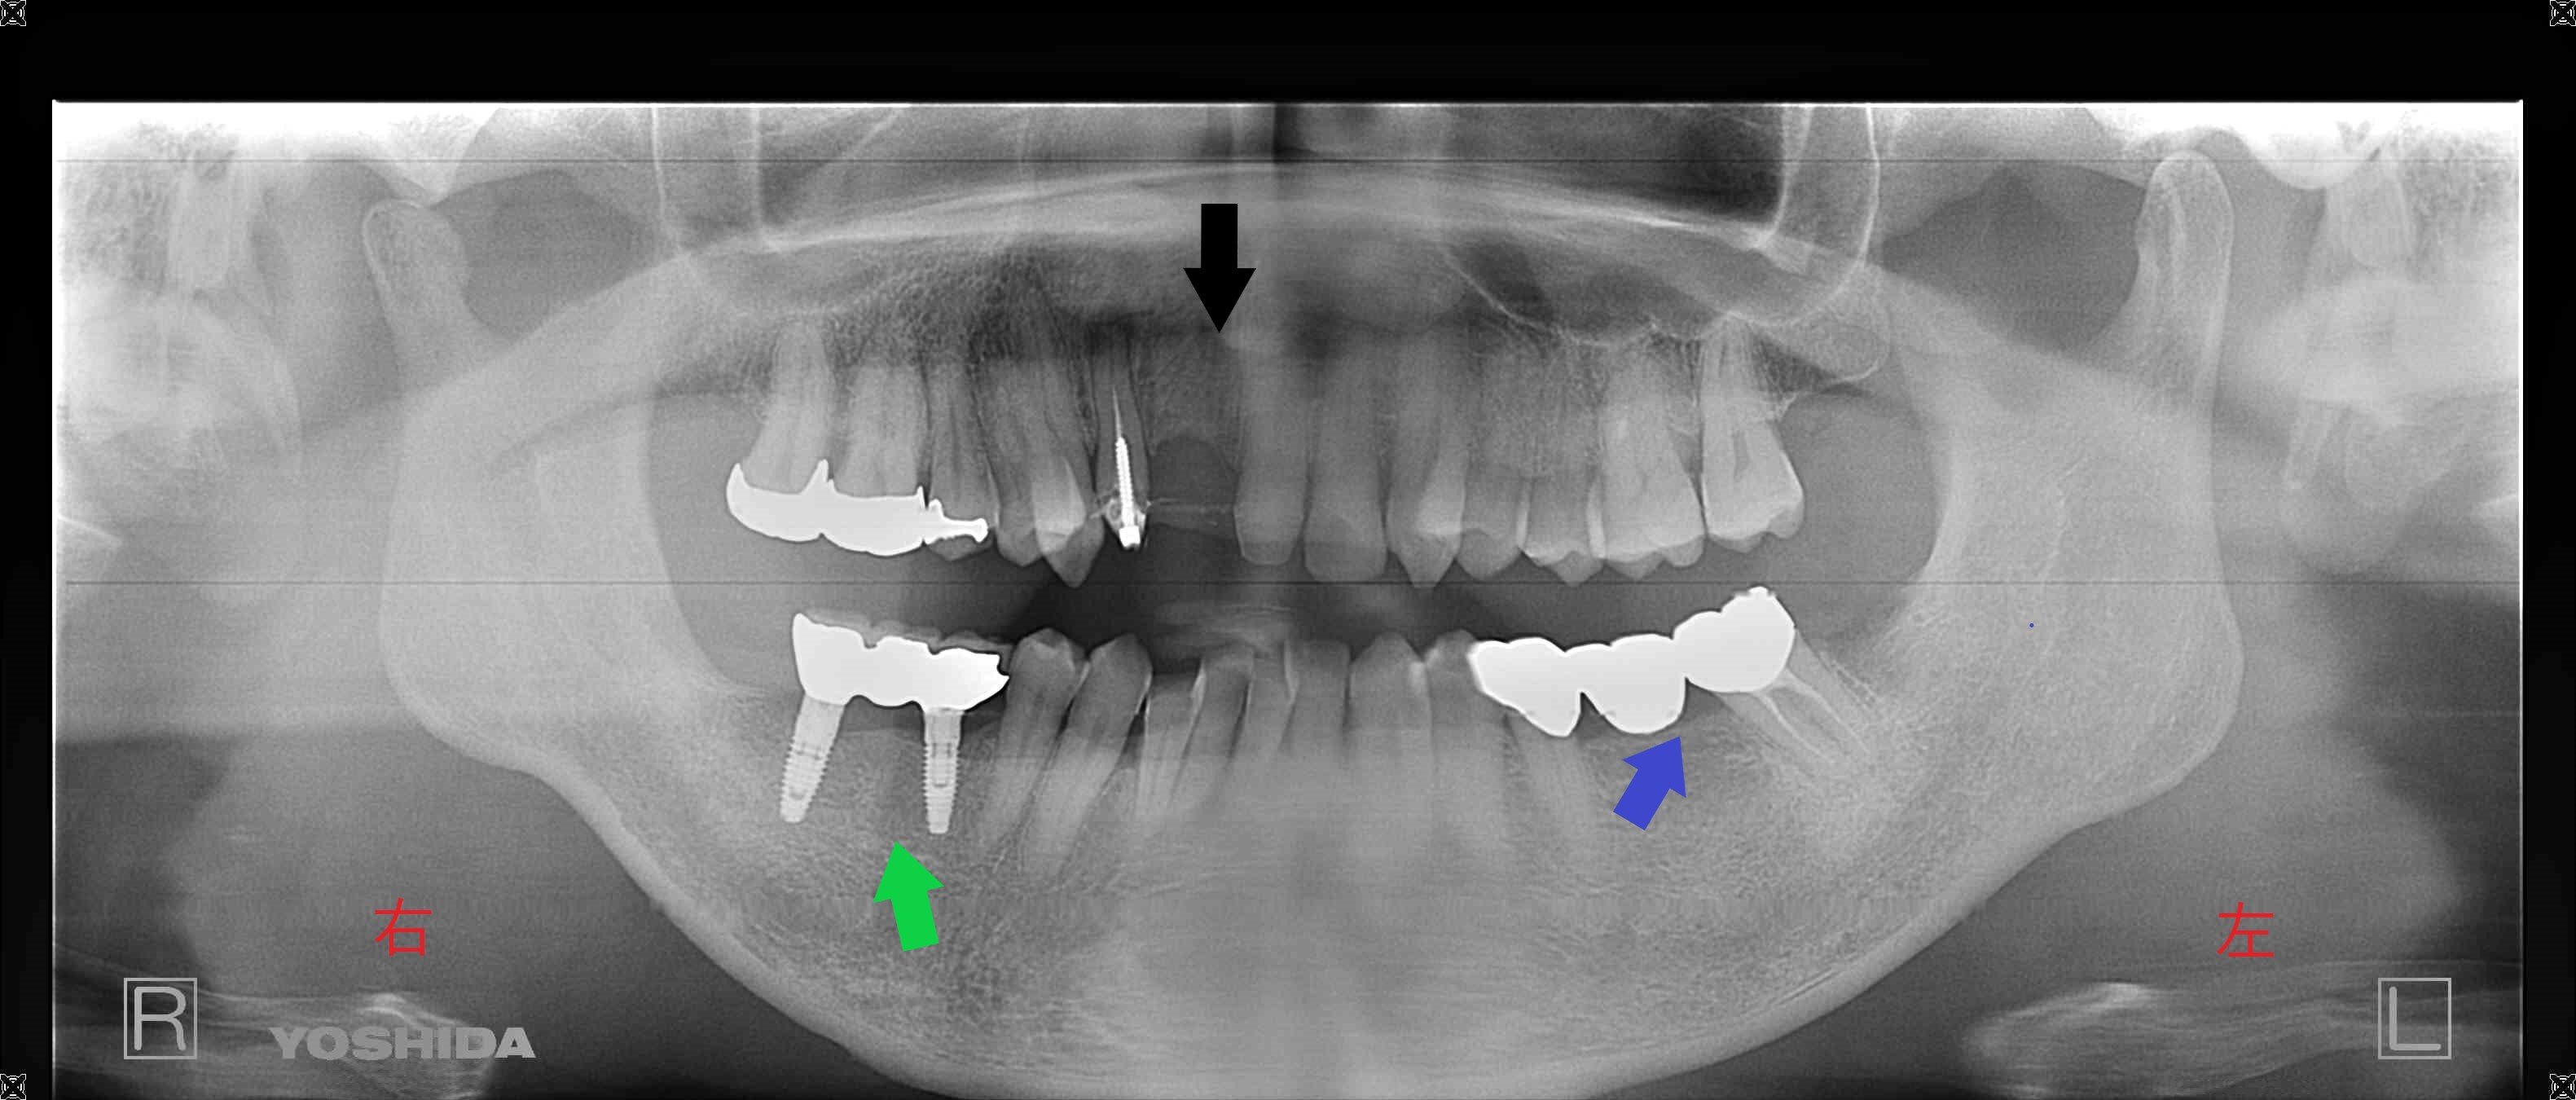

下のレントゲン写真は、インプラント治療後の様子です(緑色矢印)。

左下のブリッジ(青色矢印)についても、患者様は再度ブリッジによる治療を希望されました。虫歯が大きかったため、神経を除去する処置が必要となり、結果として歯の強度が低下し将来的に歯根破折のリスクが高まる点をご説明のうえ、患者様のご意向を踏まえた治療を行いました。

治療期間は6か月、通院回数は7回、治療費はインプラント2本、GBR(骨造成)、外科用ステント、ハイブリッド冠3本を含めて799,200円(税込)でした。

さらに別の写真では、左上前歯(黒色矢印)に大きな虫歯があり、穴があいている様子が確認されました。治療後は、メタルボンド(セラミックを使用した被せ物)によるブリッジを装着しています。これは、保険適用の素材に比べて変色しにくく、歯垢(プラーク)も付着しにくいため、虫歯や歯周病の予防にも配慮された素材です。